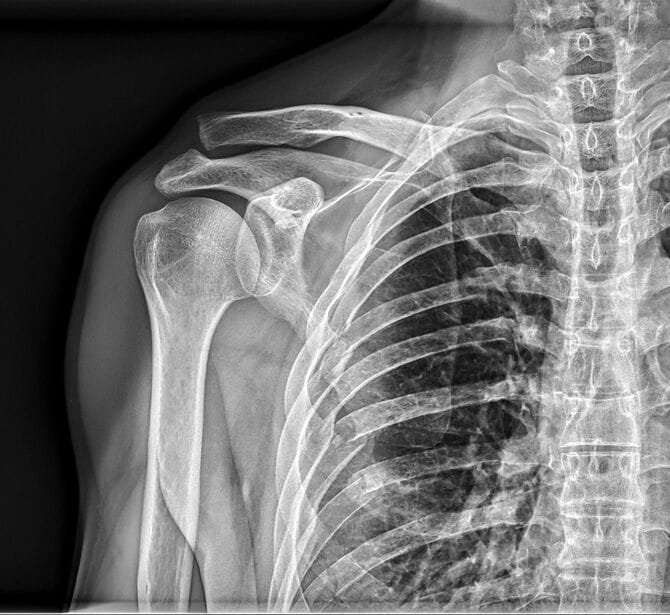

その時担当医が来て、レントゲン写真を見せながら説明を始めた。

「母の左側の肋骨は、12本のうち9本が折れており、3本にはひびが入っていて……こんなにボッキボキに骨折していても、コルセットを付けるぐらいしか処置の方法がありませんでした。また、医師は『お母さんは一人暮らしとのことですが、何もなければ2~3日で退院になる。退院後は実家で誰かが世話するのか、リハビリができる施設に身を寄せるのか、ソーシャルワーカーと相談してください』と言われました」